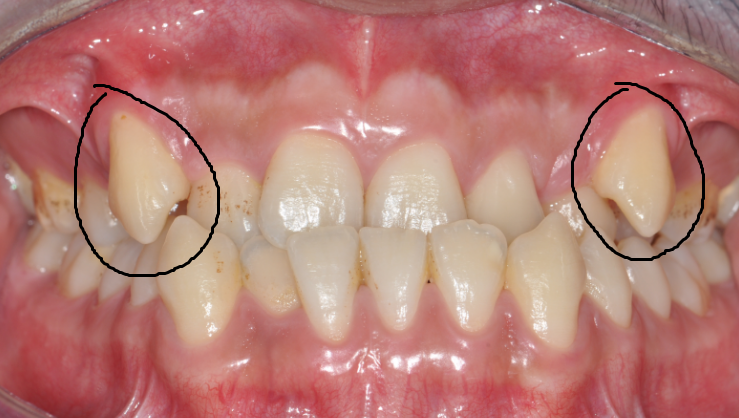

齒 嘿嘿,牙妹,我覺(jué)得我的牙齒距離就差一點(diǎn)兒了。你看我的虎牙,長(zhǎng)出來(lái)的位置不正,被擠在牙弓外面,一張嘴就會(huì)看見(jiàn),很不美觀。別的牙還挺齊的,所以我想能不能直接把虎牙拔掉,這樣就用簡(jiǎn)單的方法解決了問(wèn)題。(圖片1 2)